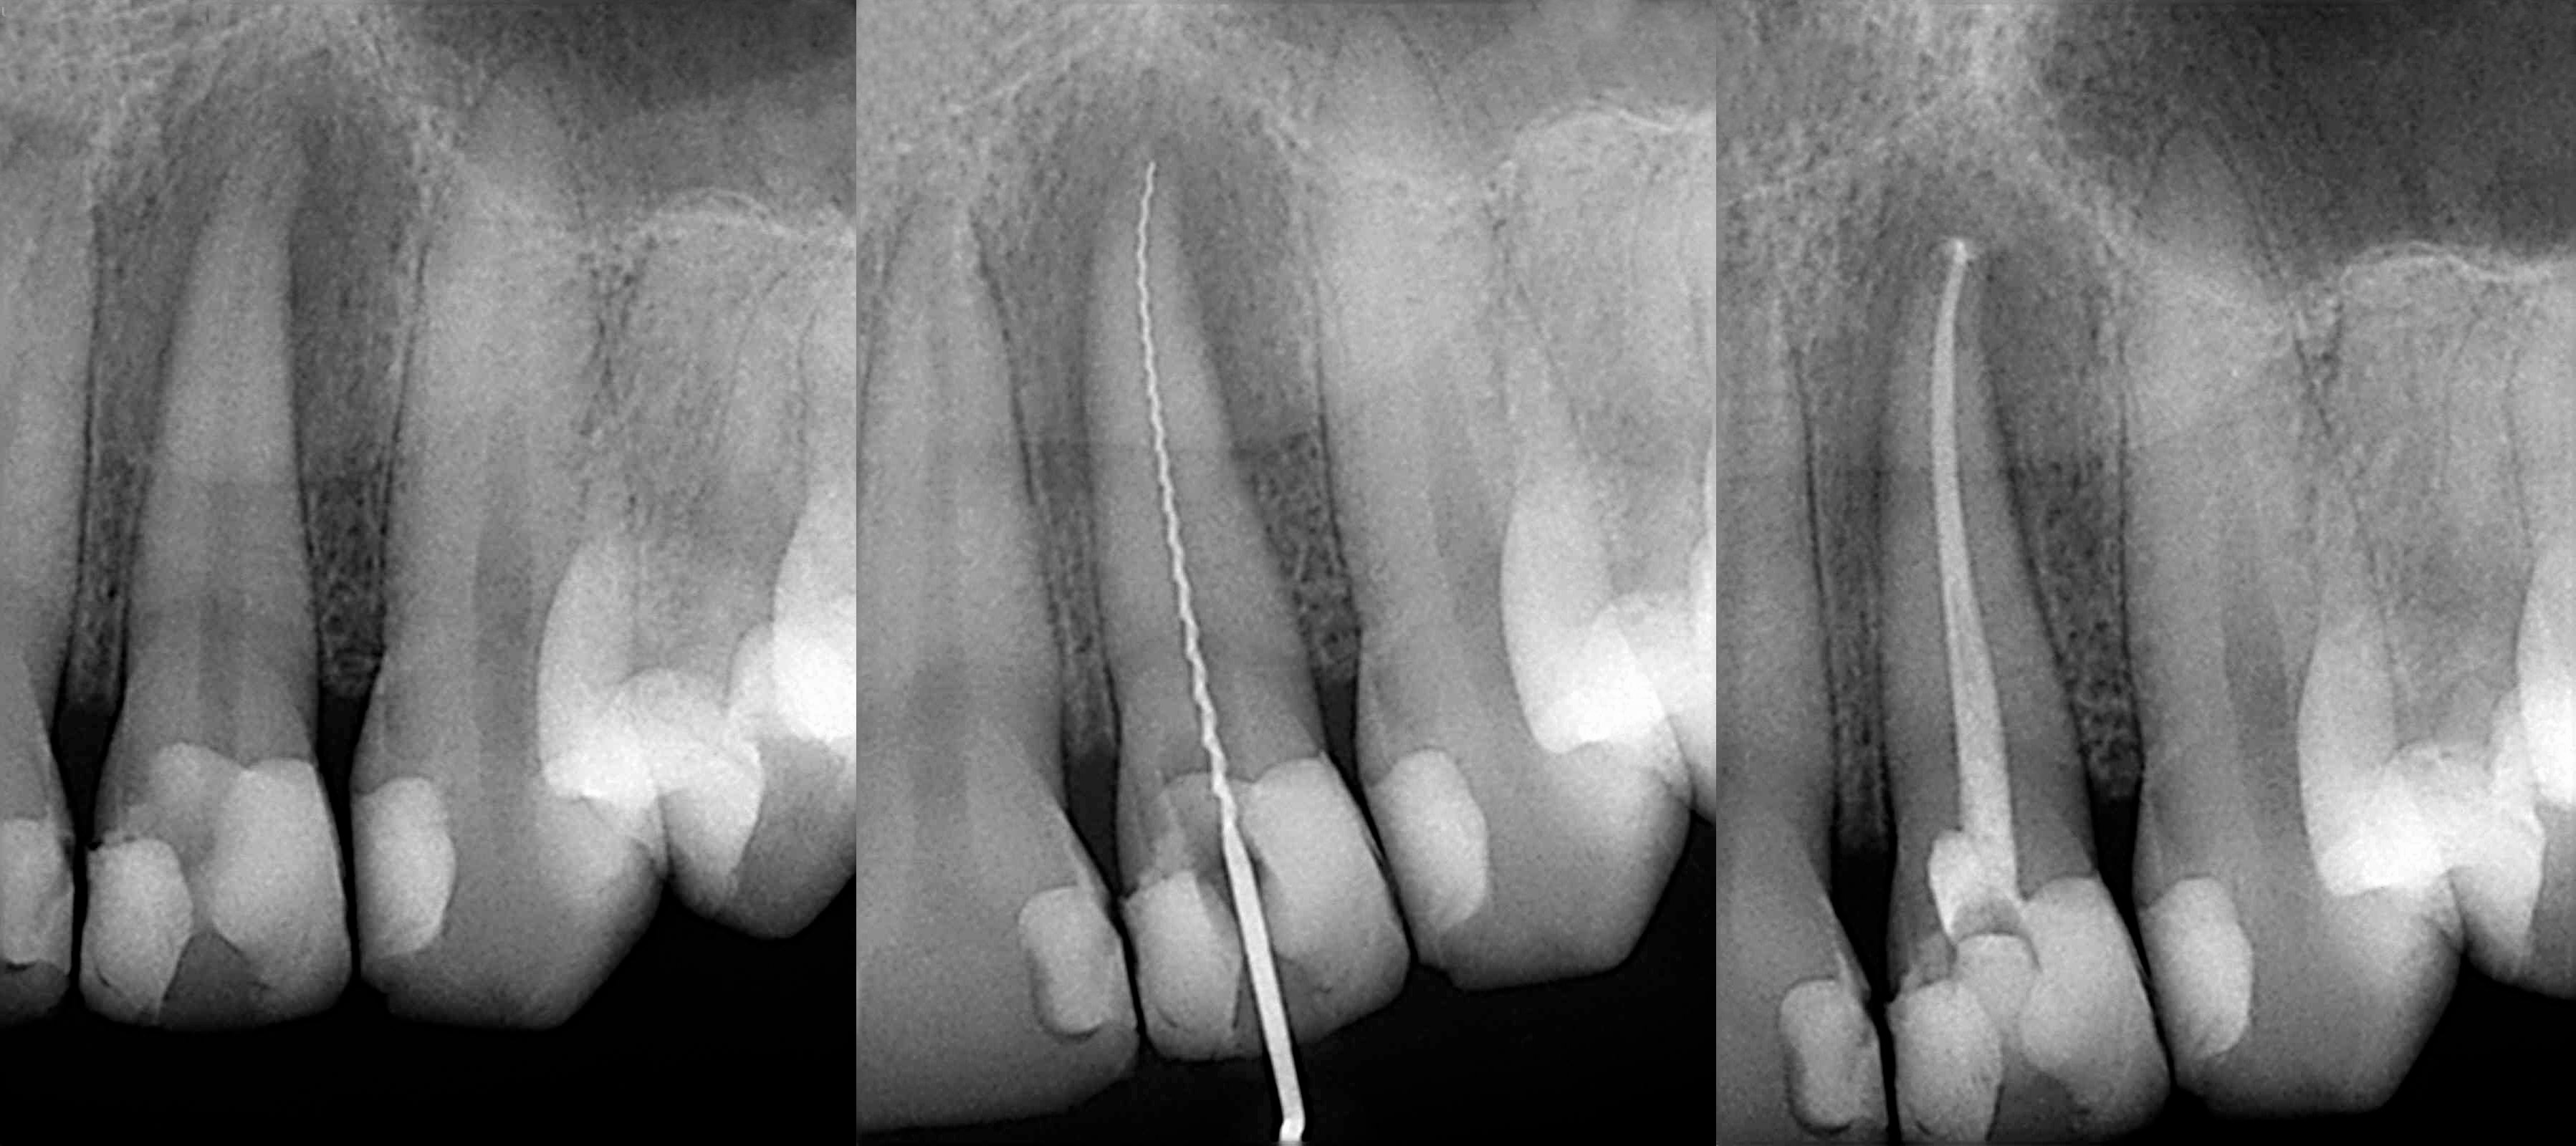

傳統根管治療只能依靠牙醫師的肉眼或手感,但若遇到堵塞、狹窄鈣化、穿孔分岔、帶狀根管等特殊狀況時,傳統根管治療很難做到理想的治療效果。

使用牙科專用顯微鏡可提高困難根管治療的成功率,因為牙醫師用放大 20 倍以上顯微鏡較易辨認肉眼無法找到的根管、齒壁上的小裂痕或斷裂的器械;顯微鏡結合超音波振盪沖洗可將複雜彎曲的根管系統做更透徹的消毒,降低根管中殘留細菌的機會。

顯微根管治療流程

• 施打局部麻藥與置放牙齒隔離障

• 清除蛀牙與填補物,打開髓腔

• 顯微鏡下擴大根管與超音波沖洗

• 完成根管系統清洗後封填

• 製作贋復物:牙冠、牙套、嵌體、補牙